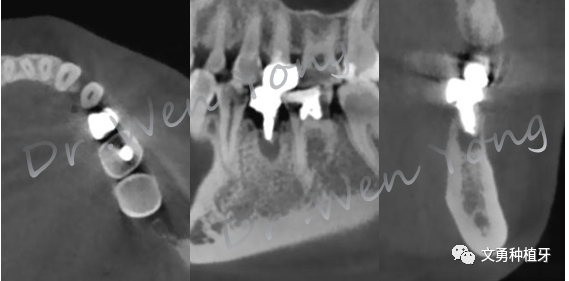

2、术前CBCT示:75根尖周低密度影,颊侧骨板完整

3、CBCT回顾整个治疗过程